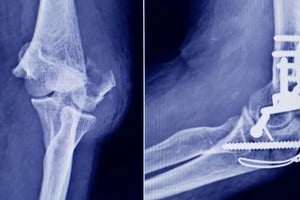

El procedimiento, realizado a fines de 2025, puso al descubierto un escenario preocupante: la presencia de un tornillo quirúrgico falsificado y otros implantes de origen desconocido, sin respaldo documental ni registro sanitario. La medida quedó formalizada en la Disposición 2223/2026, publicada en el Boletin Oficial, y tiene alcance en todo el territorio nacional.

El caso más relevante fue el de un tornillo de interferencia para ligamento cruzado, rotulado como perteneciente a la marca Stryker. Tras un análisis detallado, se determinó que se trataba de una falsificación.

Las diferencias con el producto original fueron contundentes. Mientras el implante legítimo presenta un color gris opaco, el detectado era incoloro y translúcido, lo que sugiere una composición distinta. Además, el empaque no coincidía con los estándares del fabricante: estaba contenido en una bolsa tipo pouch de una marca que no es utilizada por la empresa original.

Otro punto clave fue el método de esterilización. El producto auténtico se esteriliza mediante radiación gamma, mientras que el hallado indicaba haber sido preparado para esterilización por vapor o formaldehído, un procedimiento incompatible con ese tipo de dispositivo.

En el caso del tornillo falsificado, la incertidumbre sobre su composición y resistencia mecánica abre la posibilidad de fallas estructurales una vez implantado. En cirugías como las de ligamento cruzado, este tipo de dispositivos cumple una función clave en la estabilidad de la articulación.